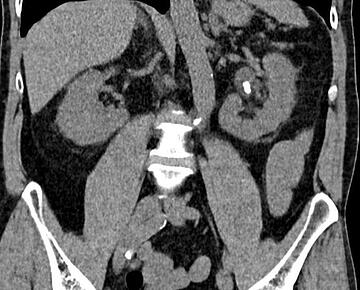

Computertomographie mit dem Nachweis eines Nierenbeckensteines links

Die Diagnostik besteht aus der Abklärung der Symptome, körperlicher Untersuchung, Urin- und Blutlabor sowie einer Bildgebung. Die Standard-Bildgebung besteht zunächst aus einer Ultraschalluntersuchung, gefolgt von einer Computertomographie (Low-Dose CT mit niedriger Strahlenbelastung). Durch die Untersuchung mittels CT ist es möglich, selbst Steine darzustellen, die aufgrund ihrer Zusammensetzung im konventionellen Röntgen nicht zur Darstellung kommen (z.B. Harnsäuresteine).